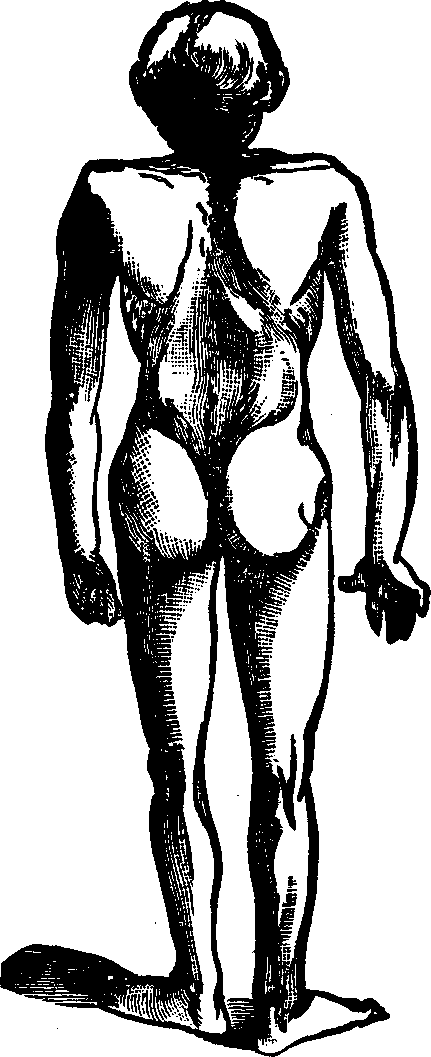

Absence of the Ovaries. Let us suppose the case of a young woman who has fully reached the period of puberty without having menstruated. All the organs which we have described, are manifestly developed, she is healthy, vigorous, robust, and able to exercise freely or to engage in laborious occupations. But we notice that her voice is not sweetly feminine, nor is her presence timid, tender, and winning; there is wanting that diffident sexual consciousness, which gently woos, and, at the same time, modestly repels, and tends to awaken interest, curiosity, and desire. Considering also that she has never manifested any inclination to menstruate, we are irresistibly led to the conclusion that the ovaries are wanting; the delicate mustache upon the upper lip, the undeveloped breasts, the coarse features, and her taste for masculine pursuits, all concur in this diagnosis. Thus we account for the harshness of the voice, fitted for command rather than to express the mellow, persuasive cadences of love. Such a malformation cannot be remedied.

Symptoms. The sufferer from leucorrhea becomes pale and emaciated, the eyes dull and heavy, the functions of the skin, stomach and bowels become deranged, more or less pain in the head is experienced, sometimes accompanied with dizziness, palpitation is common, and, as the disease progresses, the blood becomes impoverished, the feet and ankles are swollen, the mind is apprehensive and melancholy, and very frequently the function of generation is injured, resulting in complete sterility. Exercise produces pain in the small of the back and the lower portion of the spine, and, owing to a relation of the vaginal walls, the womb falls far below its natural position, or turns in various directions, according to the manner in which the weight above rests upon it. Ulcers are apt to appear upon the mouth of the womb, the matter from which tinges the discharge and stains the linen. Hysteria is often an attendant of this disease.